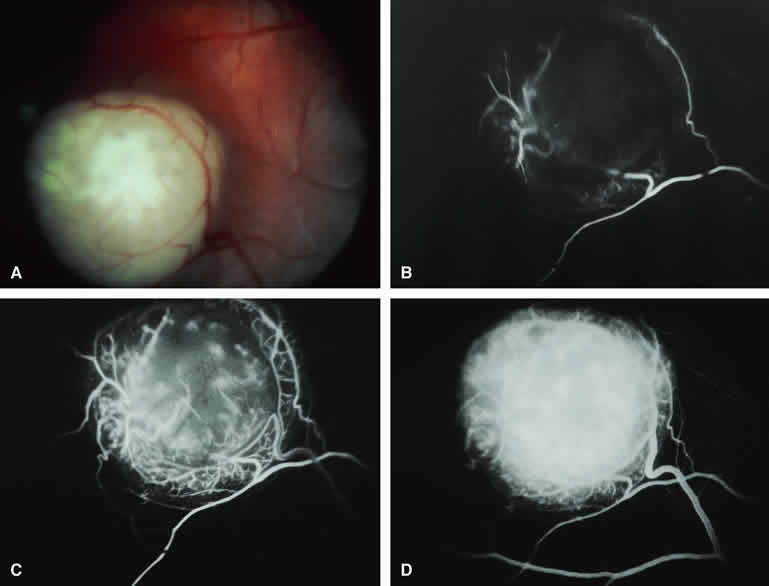

Amelanotic Choroidal Nevus

Approximately 10% to 15% of choroidal nevi are largely or completely amelanotic clinically. Fluorescein and ICG angiography of an amelanotic choroidal nevus (see Fig. 3) tend to show less prominent hypofluorescence of the lesion than they do with darkly melanotic nevi. Because of the lack of intracellular melanin pigment within the nevus cells, some large-caliber choroidal blood vessels running through the nevus may be visible in the region of the mass (see Fig. 3B and C). These choroidal blood vessels are better defined by ICG angiography than by fluorescein angiography. Amelanotic choroidal nevi often appear mildly hyperfluorescent in late-phase frames (see Fig. 3D).